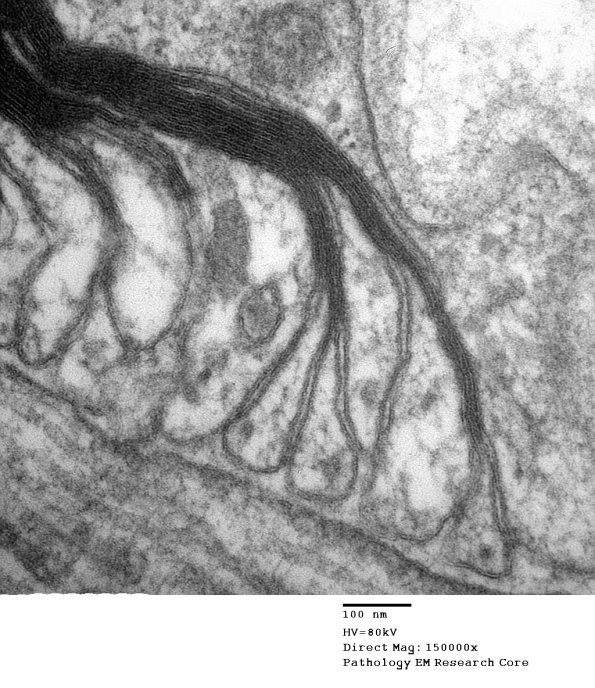

These high magnification images show the myelin loops interacting with adjacent axolemma which has sub-axolemmal densities. (electron micrographs)